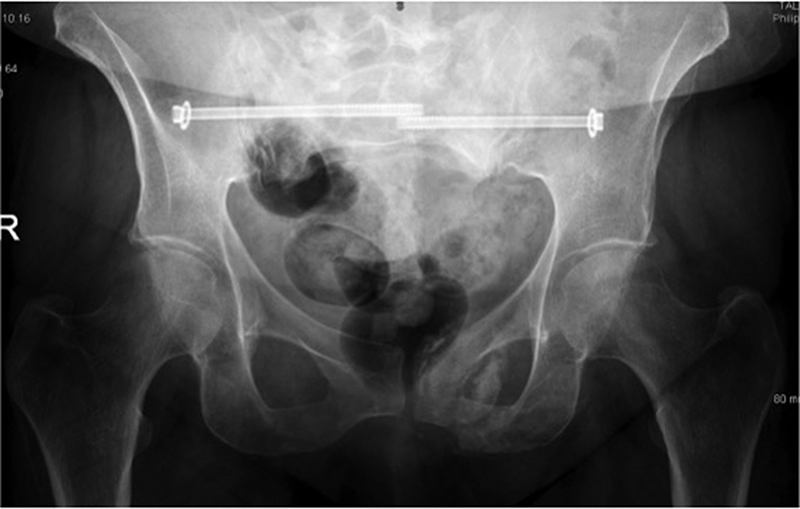

The sacroiliac joint (SIJ) is the largest axial joint in the musculoskeletal system and its primary responsibility is to transfer the weight of the upper body to the lower extremities. In the past this joint has been largely ignored as a pain generator, however, recent research has reported that the sacroiliac complex may be the source of pain in 15-25% of all individuals who present with low back problems.1 To avoid unnecessary lumbar spine surgery, SIJ disorders should be strongly considered in low back pain diagnosis.2

The sacroiliac joints are composed of the sacrum wedged between the ilia. It is the largest axial joint in the human body, with a surface area of approximately 17.5cm2. The morphology of the SIJ not only changes with age but it also varies greatly in size, shape and contour from side to side as well as between individuals.

The surface of the joint is flat until after puberty. By age 30, bony ridges are present on the articular surface of the ilium. With time the synovial articular surfaces erode and the synovial cleft narrows. The joint is supported by numerous ligaments, muscle and fascia.

Pathology

The most common cause of SIJ pain is idiopathic and may occur acutely or insidiously with cumulative trauma. Idiopathic SIJ pain may result from a change in the joint’s position or mechanics. Other potential causes include:

- Trauma

- Osteoarthritis

- Infection

- Inflammatory conditions (sacroiliitis is present in virtually 100% of individuals with ankylosing spondylitis)

- Metabolic conditions (for example, gout and renal osteodystrophy)

- Malignancy – metastases to the pelvis account for 40% of all osseous metastasis, second only to those of the spine and iatrogenic, for example, post bone graft harvesting, lumbar spine fusion).

Insufficiency sacral fractures in the older osteoporotic patient may occur with little or no trauma, and can be difficult to visualise on plain radiographs. Stress fractures have been reported in athletes due to repetitive microtrauma caused by impact loading over long periods of frequent physical exertion.